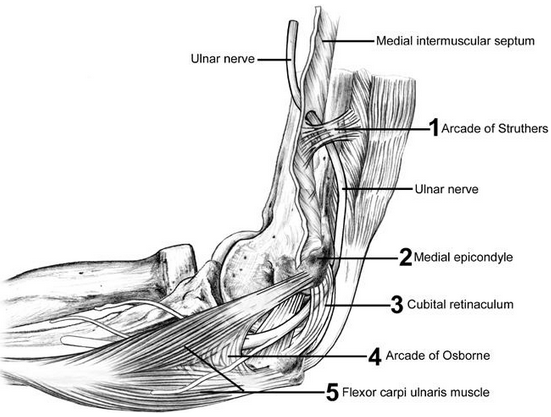

Course of the ulnar nerve

From medial cord

Runs in anterior compartment of arm, posteromedial to brachial artery

Pierces medial intermuscular septum at arcade of struthers ~8cm from the medial epicondyle, lying medial to triceps

Run behind medial epicondyle with superior ulnar collateral artery

Entes cubital tunnel

Enters forearm between 2 heads of FCU

Runs between FCU & FDP

In the wrist & had via Guyon’s canal